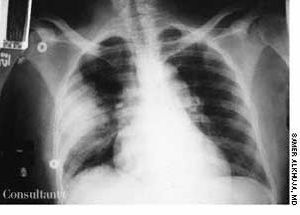

A febrile 65-year-old woman who had suffered a new-onset seizure was brought to the emergency department. The patient-a cigarette smoker-was not coughing and had neither chest pain nor a significant medical history. Her temperature was 39.4°C (103°F). She had nuchal rigidity and Kernig's and Brudzinski's signs of meningeal irritation. Lung auscultation revealed signs of right middle lung consolidation. Her white blood cell count was 1,200/µL. A chest film, seen here, showed a masslike density in the right midlung.